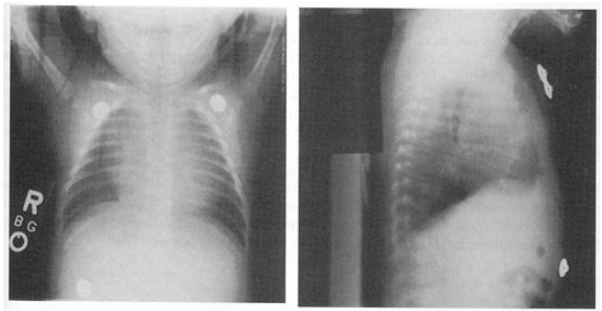

61.下列何者不是造成呼吸器病人產生呼吸窘迫的可能原因? (A)病人呼吸驅動力不足 (B)呼吸器管路漏氣 (C)呼吸器 FiO

62.5週大女嬰因疑似心臟擴大被轉診,昨晚因躁動不安與上呼吸道症狀到某醫院就診,胸部X光如圖,理 學檢查時,外觀正常,活動力佳,心搏每分鐘145次、呼吸40次、血壓70/45毫米汞柱,血氧飽和度為 95%,肝臟在右肋緣下1公分。下列敘述何者正確?

(A)可能為心肌炎前兆 (B)可能為先天性心臟病 (C)縱膈腔有腫瘤 (D)正常嬰兒